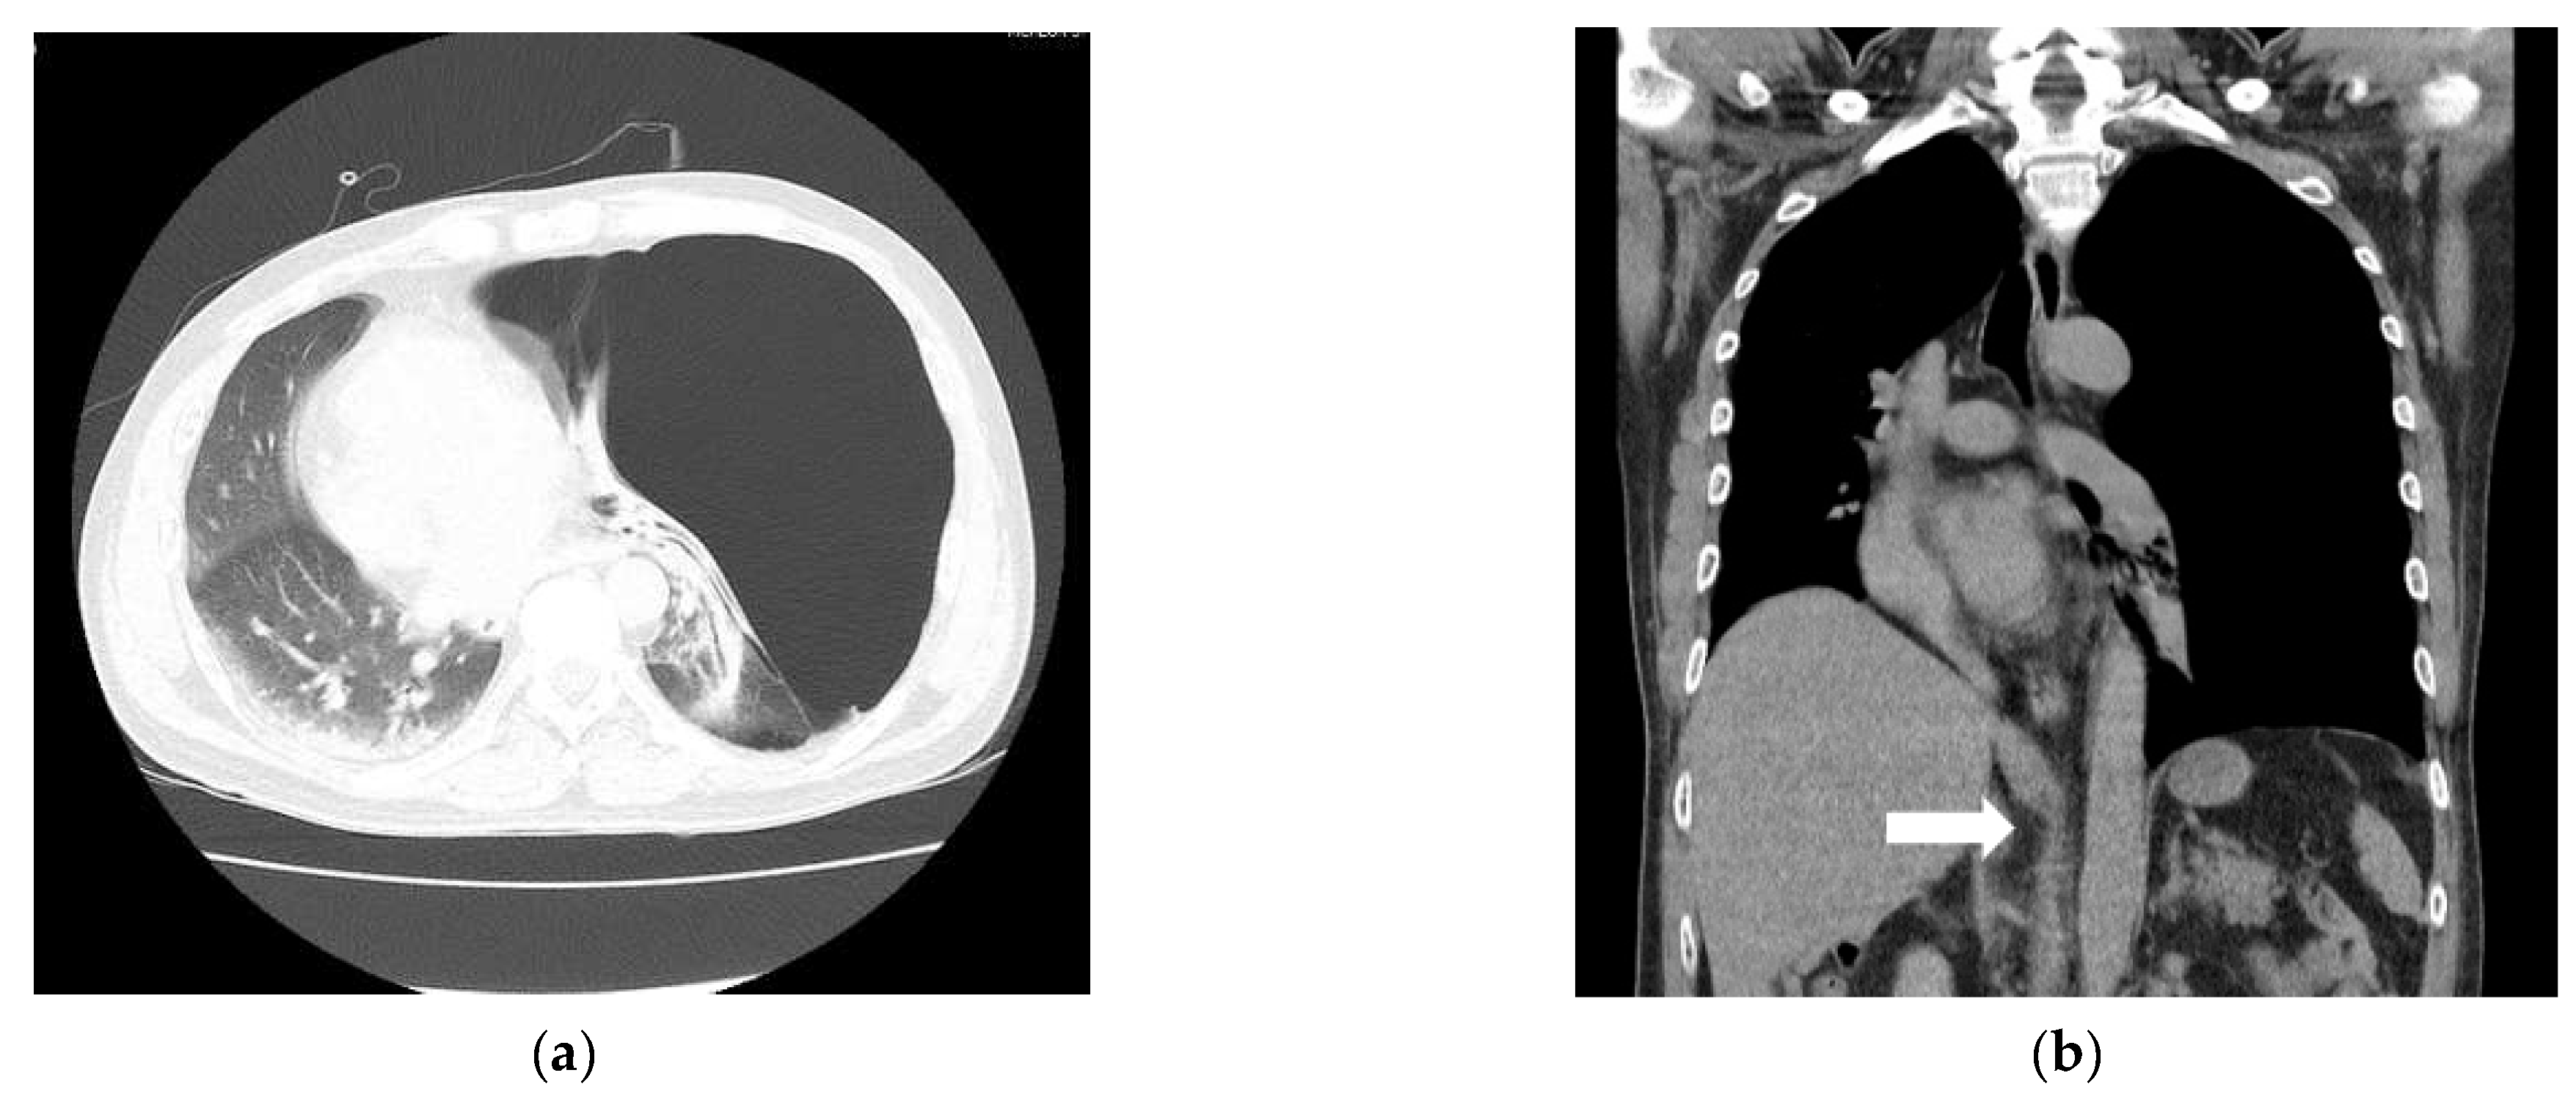

Other diseases and surgical history were denied. His vital signs in the emergency room were stable with a blood pressure (BP) of 145/90 mmHg, a heart rate (HR) of 89 bpm, a respiratory rate of 20 per minute, a SpO2 level of 97%, and a body temperature of 36 °C. An abdominal CT scan showed active bleeding in the right rectus sheath muscle and hemoperitoneum. Thus, emergency surgery was decided upon. There were no abnormal preoperative laboratory findings or electrocardiographic findings. A chest X-ray showed a large radiolucent area of the left lung with contralateral mediastinal deviation, so the emergency medicine physician suspected a pneumothorax. The pneumothorax seen on the X-ray was large, but the patient had no pneumothorax symptoms, such as dyspnea or chest pain. Therefore, a chest CT was performed. However, the CT showed a GEB in the left lung and bullous emphysema in the right lung with displacement of the mediastinal structures (Figure 1a and Figure 2a). In cases with GEBs, unlike with a pneumothorax, chest tube drainage (CTD) is not placed because the bullae could be damaged and tension pneumothorax could occur. Although the patient had no symptoms of dyspnea, it was decided to remove the GEB first and then perform abdominal surgery in consultation with a thoracic surgeon, since the GEB could affect the patient’s vital signs during positive pressure ventilation.

After the bullectomy, the supine position was changed, and surgery was performed for the abdominal wound area. For the surgical operation, laparotomy was performed. His vital signs were stable during the abdominal surgery. The patient recovered from anesthesia with stable vital signs. The total time under anesthesia was 245 min, and the operation’s time was 215 min. The patient was transferred to the intensive care unit, where his vital signs remained stable. The patient was transferred from the intensive care unit to the general ward after 16 h. A chest X-ray taken on the second day after the surgery showed no special findings (Figure 1b). The chest tube drainage was removed on the 8th day after the operation. The patient was discharged without complications on the 12th day after the operation.

For the diagnosis of a GEB, a chest X-ray is primarily performed. X-ray findings have shown large bullae that account for one-third of the hemithorax, lung parenchyma atelectasis, inverted ipsilateral diaphragm, and contralateral displacement of the mediastinum [8]. GEBs and pneumothorax are different in chest X-rays. In the chest CT scan, there was no pneumothorax, but giant bullae were shown over the entire lung. In the case of a GEB, the entire parenchyma is compressed downward in the direction of the costal angle, while a pneumothorax appears as a lung parenchyma that collapses into a clump toward the hilum [9]. However, plain chest X-rays and physical examinations cannot provide accurate anatomical information on the findings. In addition, if a CTD is mistakenly inserted for a pneumothorax, the GEB, which has a very thin wall compared to the normal lung parenchyma, is easily damaged and can lead to a dangerous situation, such as tension pneumothorax. Therefore, chest CT is more appropriate as a test for differentiating GEBs [10]. CT can also be a good test, as it can diagnose other coexisting diseases. In the present case, the left lung was radiolucent on chest PA, and the mediastinum was deviated to the right, suggesting tension pneumothorax (Figure 1a). In the chest CT scans, it was revealed that it was not a pneumothorax, as giant bullae were shown over the entire lung. These giant bullae caused a mass effect that deviated the mediastinum (Figure 2a). In addition, it could be seen that the inferior vena cava (IVC) was bent due to the mediastinal shift in the coronal plane of the chest CT (Figure 2b). This can lead to cardiovascular collapse due to the mass effect of the GEB itself, as well as tension pneumothorax due to the rupturing of the GEB. We speculate that this mass effect might have been exaggerated by muscle relaxation after succinylcholine use. Superior vena cava syndrome caused by a GEB pressing the superior vena cava has been reported [11]. However, cases showing IVC-syndrome-like symptoms by pressing the IVC have not yet been reported.

Figure 1. Chest X-ray at the time of admission (a) and on the first day after the operation (b). It can be seen that the left lung collapsed, and the mediastinum shifted to the right (a).